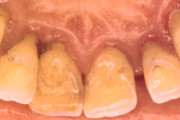

Krooniline parodontiit

Krooniline parodontiit on mikroobide poolt põhjustatud hammaste tugikudede põletik, mille tulemusena tekib progresseeruv alveolaarluu (nähtav röntgenograamil) ja periodontaalligamendi destruktsioon, igemetaskute moodustumine, igeme retsessioon või mõlemad kahjustused kombineeritult. Loe edasi »

- igemepiir on taandunud (3)

- luu destruktsioon (5)

- puudulik suuhügieen (5)

- igemepealne hambakivi (5)

- igemealune hambakivi (4)